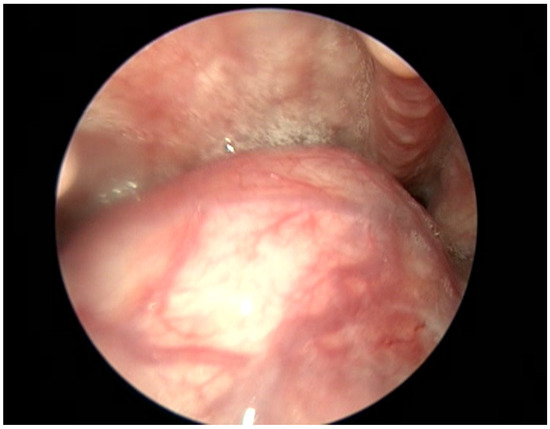

2. Case Report